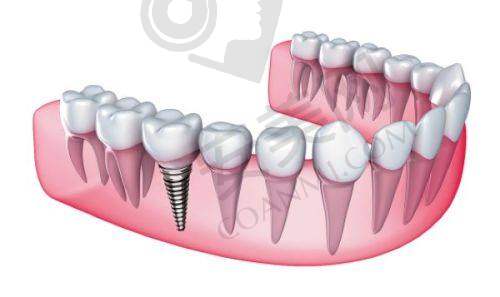

牙齿缺失会给人们的生活带来诸多不便,不仅影响美观,还会影响咀嚼功能和口腔健康。种植牙作为一种理想的牙齿修复方式,受到了越来越多人的关注。在晋城,百年口腔是一家颇具规模的口腔医疗机构,那么晋城百年口腔种植牙一颗多少钱呢?这是特别多想要进行种植牙修复的患者关心的问题。本文将为您详细介绍晋城百年口腔种植牙的价格情况,以及影响种植牙价格的因素等内容,帮助您更好地了解和选择。